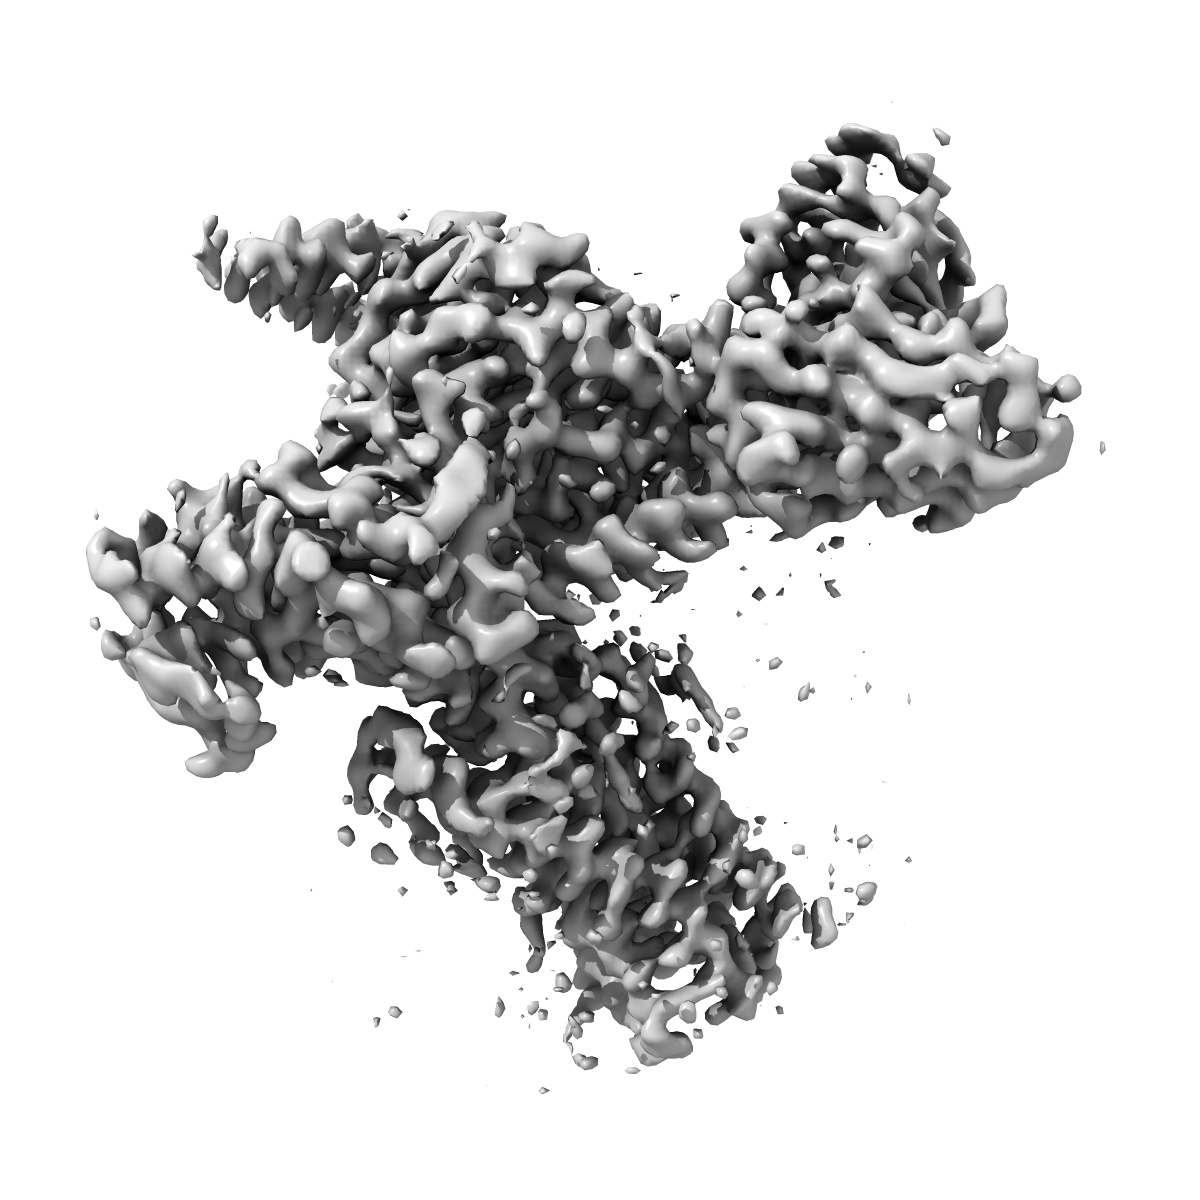

Cryo-EM structure of the DHA bound FFA1-Gq complex

Sample: DHA-FFA1-miniGq complex

Structural basis for the ligand recognition and signaling of free fatty acid receptors.

Zhang X , Guseinov AA , Jenkins L, Li K , Tikhonova IG , Milligan G , Zhang C

(2024) Sci Adv , 10 , eadj2384 - eadj2384